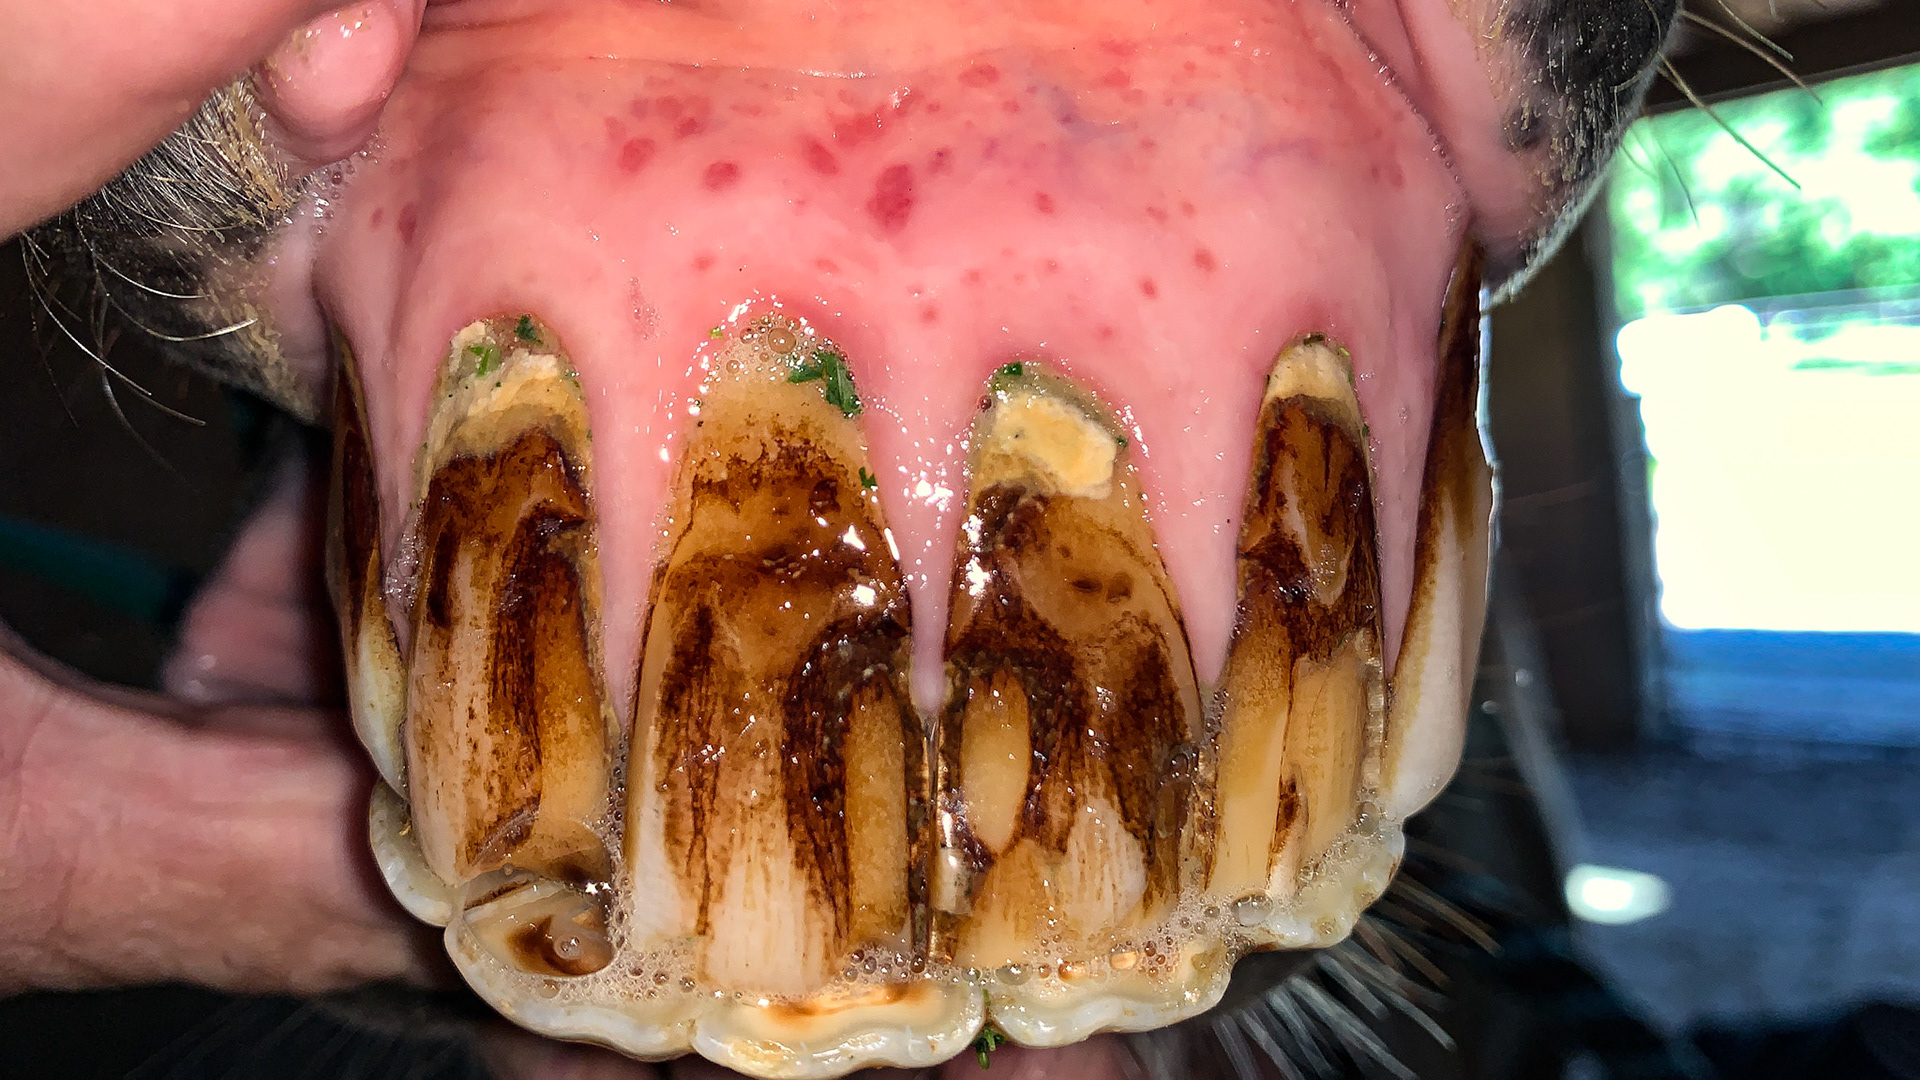

ETORH horse 5 - with loose, painful, & necrotic incisors. Excessive tartar due to tongue not moving over the painful teeth.

ETORH horse 5 - with loose, painful, & necrotic incisors. Excessive tartar due to tongue not moving over the painful teeth. Extracted with IV sedation and analgesics. Horse went right to eating without difficulties afterwards.